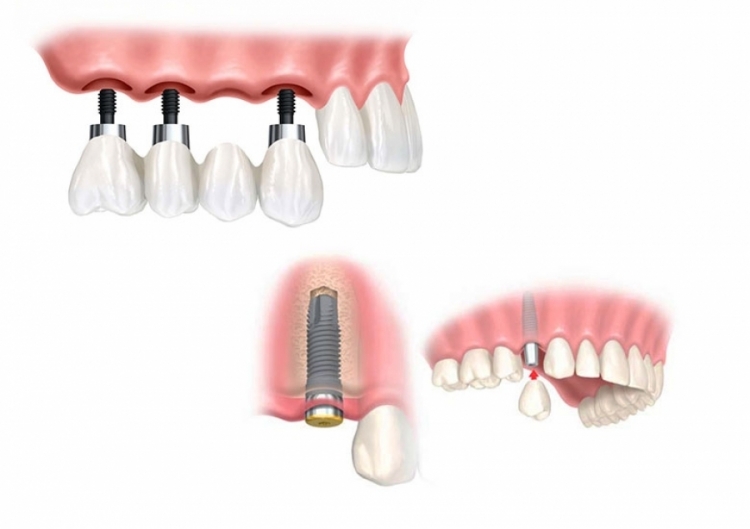

Ponti e Corone su Impianti a Vite

Durante i controlli, possono essere anche smontati per la pulizia. Le sovrastrutture protesiche fissate con viti richiedono una lavorazione tecnica complessa e sono pertanto più costose.

Le corone, quando fissate alla vite, sono ricoperte da un materiale restaurativo che imita il colore naturale dei denti, come il composito.

Protesi su Più Impianti

Le dentiere supportate da impianti sono ideali per chi ha perso un’intera arcata di denti, sia superiore che inferiore.

Molti impianti dentali fungono da ancoraggio per una dentiera personalizzata, garantendo stabilità e prevenendo problemi come lo scivolamento o il disagio.

Si possono usare 2, 3, 4 o più impianti, in acrilico, perfettamente stabili, rimovibili individualmente per la pulizia e dotati di una barra di ritenzione implantare.